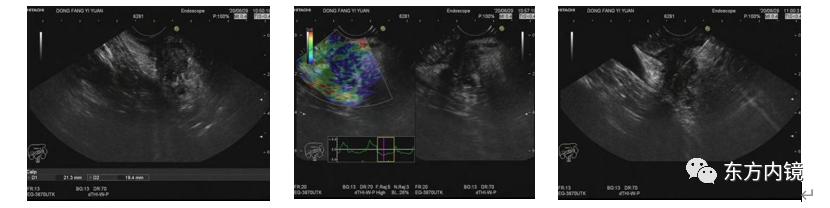

(CT及MRCP)为了明确诊断,给江阿姨做了超声内镜,在胰腺头部发现了一个2-3cm的低回声占位,超声穿刺明确诊断为胰腺癌。

(超声内镜检查及穿刺图像)外科完善检查后没有发现远处转移,及时做了手术治疗,江阿姨恢复了1个月安全出院了,术后病理提示胰腺中分化导管腺癌。

(6)超声内镜:超声内镜是对胰腺、胆总管下段局部诊断重要的手段之一,目前在诊断早期胰腺癌中越来越重要,应用越来越广泛。

近年来,通过高频探头通过内镜孔道紧贴胃十二指肠壁来检查胰腺,大大提高了对早期胰腺癌的诊断率,最小可检查出直径仅5mm且其他方法无法检出的胰腺肿块。

超声内镜还可以探测肿瘤浸润的深度、范围及淋巴结转移情况;同时,我们可以通过超声内镜做穿刺来取病理以微创手段确诊是否为胰腺癌。